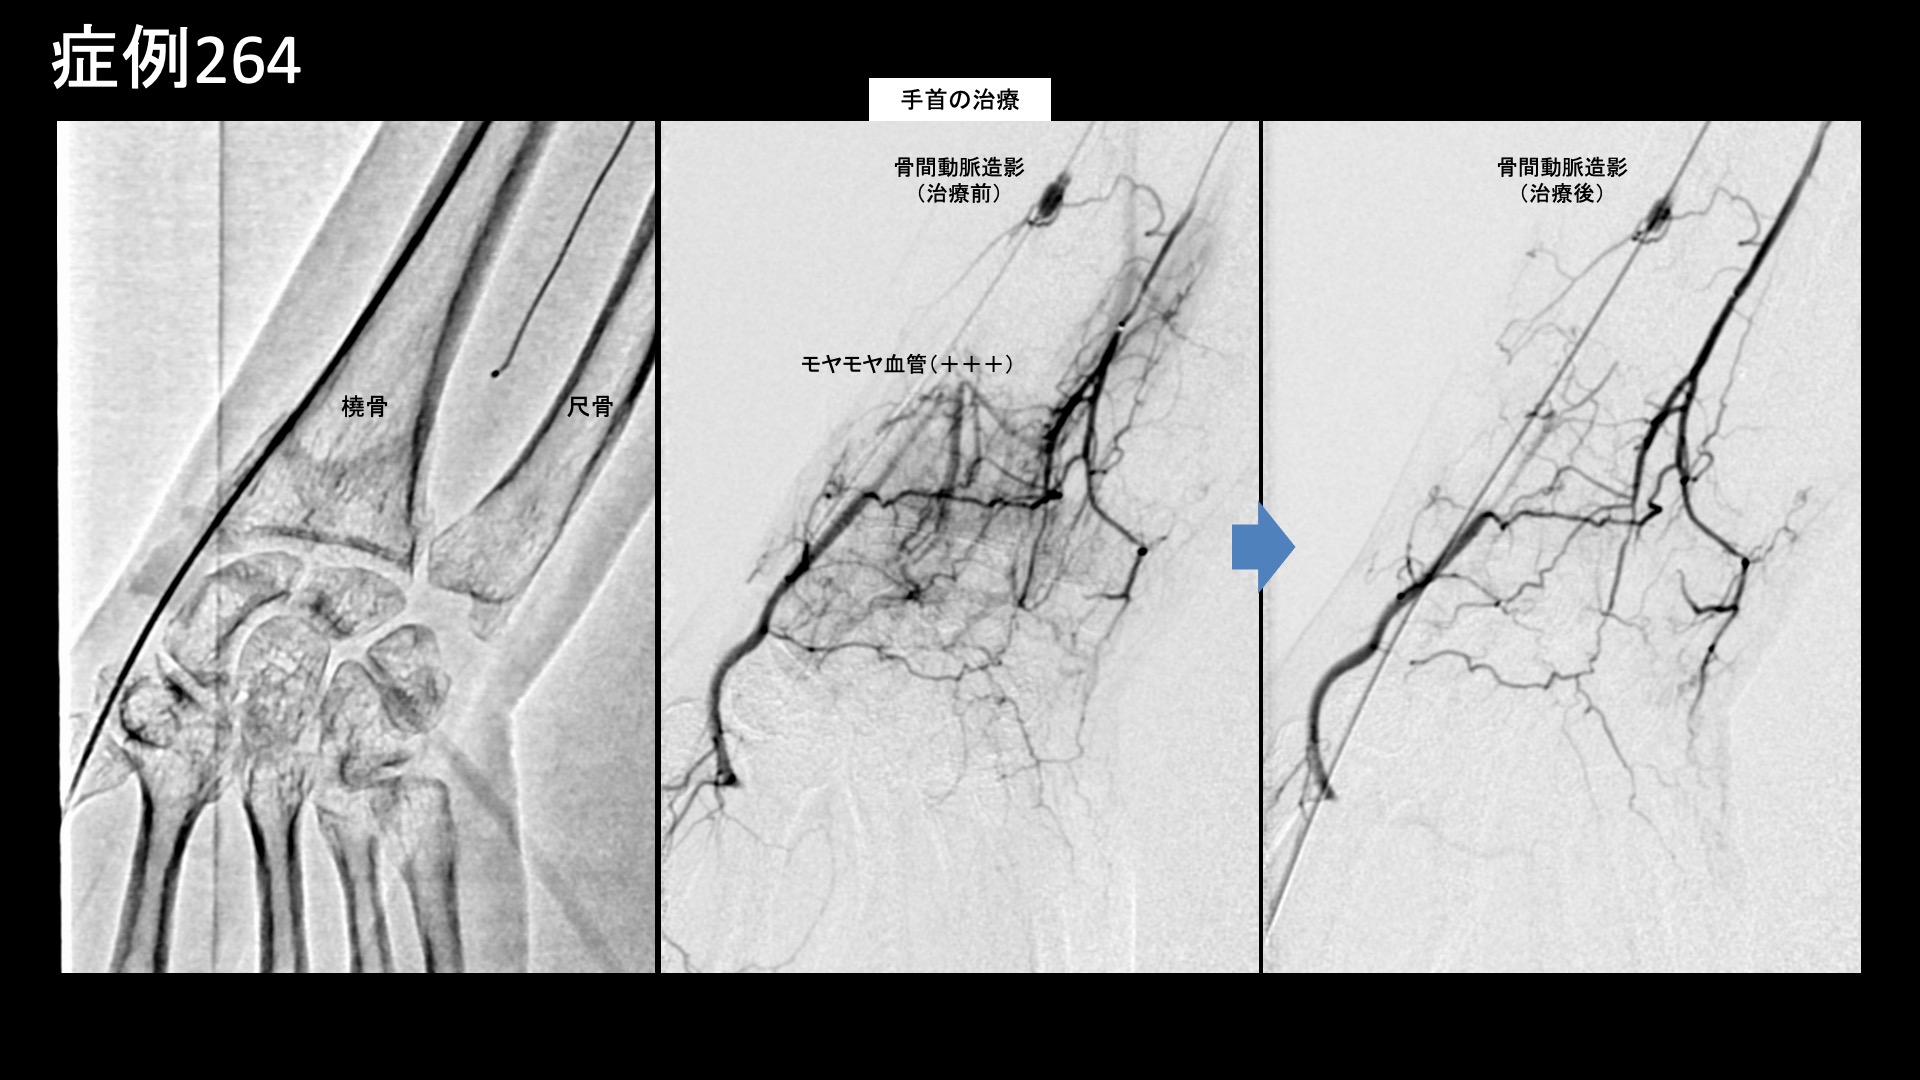

手:ばね指など 【50代:女性】骨折(橈骨遠位端骨折)治癒後も手首の小指側が痛い・・TFCC損傷および腱鞘炎に対するモヤモヤ血管治療(外傷後疼痛、橈骨遠位端骨折、TFCC損傷、尺側手根伸筋腱腱鞘炎) 2026.02.20 鴨井院長による動画解説 受診までの経過 4ヶ月前にバレーボールで手をついた際に右橈骨遠位端骨折を起こし、2ヶ月半くらいで治療が終了しましたが、その後特にきっかけなく右手首の小指側に痛みが出るようになりました。整骨院では骨折による拘縮が原因かもしれないと言われ、週2回の通院を続けましたが痛みが改善しませんでした。根本的なものを治したいと思い当院を受診されました。2ヶ月前からは五十肩も合併しており、併せて治療を希望されました。 診察時の所見 疼痛部位の特徴や、受傷機転からはTFCC損傷が疑われました。エコー検査では小指側の腱鞘炎(尺側手根伸筋腱の腱鞘炎)も合併していることが分かりました。右肩関節は自覚されていたとおり五十肩(凍結肩)で間違いありませんでしたが、比較的早期であり夜間痛は伴っておらず、動作時の痛みが主体でした。いずれも治療適応と判断し、モヤモヤ血管(病的新生血管)に対する運動器カテーテル治療(微細動脈塞栓術)を受けていただきました。 治療の所見 まず肩関節の治療を行いました。血管造影を行うと、肩関節では肩甲上動脈、烏口枝などでモヤモヤ血管が濃染像として描出されました。治療後は画像上速やかに消失しました。その他複数箇所の治療を行い終了しました。続いて右手首の治療です。TFCC損傷の主要責任血管である骨間動脈で同様にモヤモヤ血管が豊富に描出されました。骨折後でしたので、その分より多く認められたのかもしれません。両方合わせて25分程度で治療を終了しました。 治療前画像:損傷を受ける、あるいは繰り返しのストレスにより発生した異常な新生血管 治療後画像:カテーテルを用いて塞栓物質を血管内に投与し新生血管を塞いだ状態 治療費用:治療する部位によって費用が異なりますのでこちらをご参照ください。 主なリスク・副作用等:針を刺した場所が出血により腫れや痛みを生じたり、感染したりすることがあります(穿刺部合併症)。造影剤によるアレルギー(皮膚のかゆみ・赤み・息苦しくなるなどの症状)が出ることがあります。 治療後の経過 治療後、右肩は1週間経たないうちに楽になり9割程度の痛みが改善されました。動きも良くなりました。治療後2週間、右手首も術前の痛みの半分以下となりました。まだ違和感は残っており、力がまだ十分入れられませんでした。非常に経過良好でしたので、しばらく間隔を空けて治療後2ヶ月半で再診としました。右肩は引き続き順調にほとんど痛みはありませんでした。右手首も日常生活では問題なく、スポーツ復帰も果たせていました。まだスポーツの後には少し痛みが出ました。手首の背屈や回内回外動作では異常なく、エコー検査でも問題ありませんでしたので終診としています。残存症状については、安静による自然軽快が見込まれます。 TFCC損傷は局所の酷使により時間をかけて形成されることが多く、今回の受傷時に一気に悪くしてしまった可能性があります。カテーテル治療後の経過としては、すぐにカラッと良くなるというよりは、1ヶ月半くらいまでの間に、大幅に改善され、しばらく一定の少しの痛みや違和感が持続し、時間経過とともに改善されていくことが多いです。一方、スポーツなどが原因であることが多く、痛みがある程度良くなると完治していない状態でも早期から復帰したり、治療中もプレーし続けたりする方は少なくありません。酷使を続けると、良くなるのに時間がかかったり、多少の再発をしたりということもあります。治療後、少なくとも1ヶ月程度は酷使しないことが重要です。尚、実際にはただ炎症が起きているだけではなく損傷しているため、その重症度には個人差があります。正確に評価するためにはMRI検査が必要ですが、一般的にはほとんどの場合で保存的治療方針となります。モヤモヤ血管治療は非常に有力な治療選択肢ですが、本症例では骨折後遺症や腱鞘炎についても同時に治療できており、より意義が大きかったものと思われます。 TFCC損傷の詳細はこちら 【50代:女性】顔面に生じた難治の痺れと痛み、顔面骨折に三叉神経第2枝損傷を合併した外傷後疼痛に対するモヤモヤ血管治療(外傷後疼痛、顔面骨折、三叉神経第2枝損傷) 前の記事 【50代:女性】首がきしみ、肩はガチガチ、頭が重く、顎はカクカク・・2回のカテーテル治療により改善した重症首肩こりおよび頭痛・顎関節症(詳細説明あり)(首肩こり、頸肩腕症候群、頭痛、顎関節症、食いしばり(ブラキシズム)) 次の記事